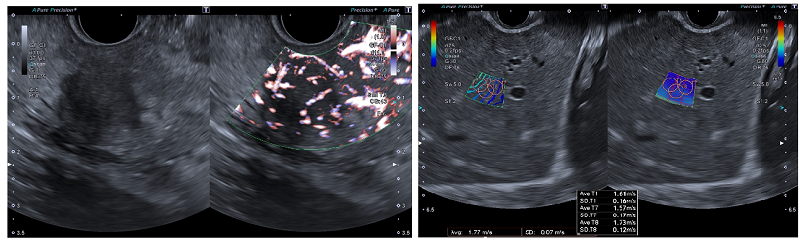

EUSをサポートする多彩な機能を搭載することで、信頼性の高い診断・治療方針の決定をサポートします。キヤノンメディカル独自技術であるSMI(Superb Micro-vascular Imaging)は、微細で低速な血流を捉える血流イメージングです。カラードプラ※1は描出困難であった低流速血流を高感度、高分解能、高フレームレート※2、低アーチファクト※3に描出できるため、超音波画像下で穿刺を行う場合でも、より安全な手技をサポートします。また、EUSで病変の炎症度や良悪性などを診断する際、病変組織の硬さに関する情報が重要な判断材料になります。SWE(Shear Wave Elastography)は組織の硬さを数値やカラーマップで表示する技術のため、より客観的な硬さの評価が可能です。

SMI SWE